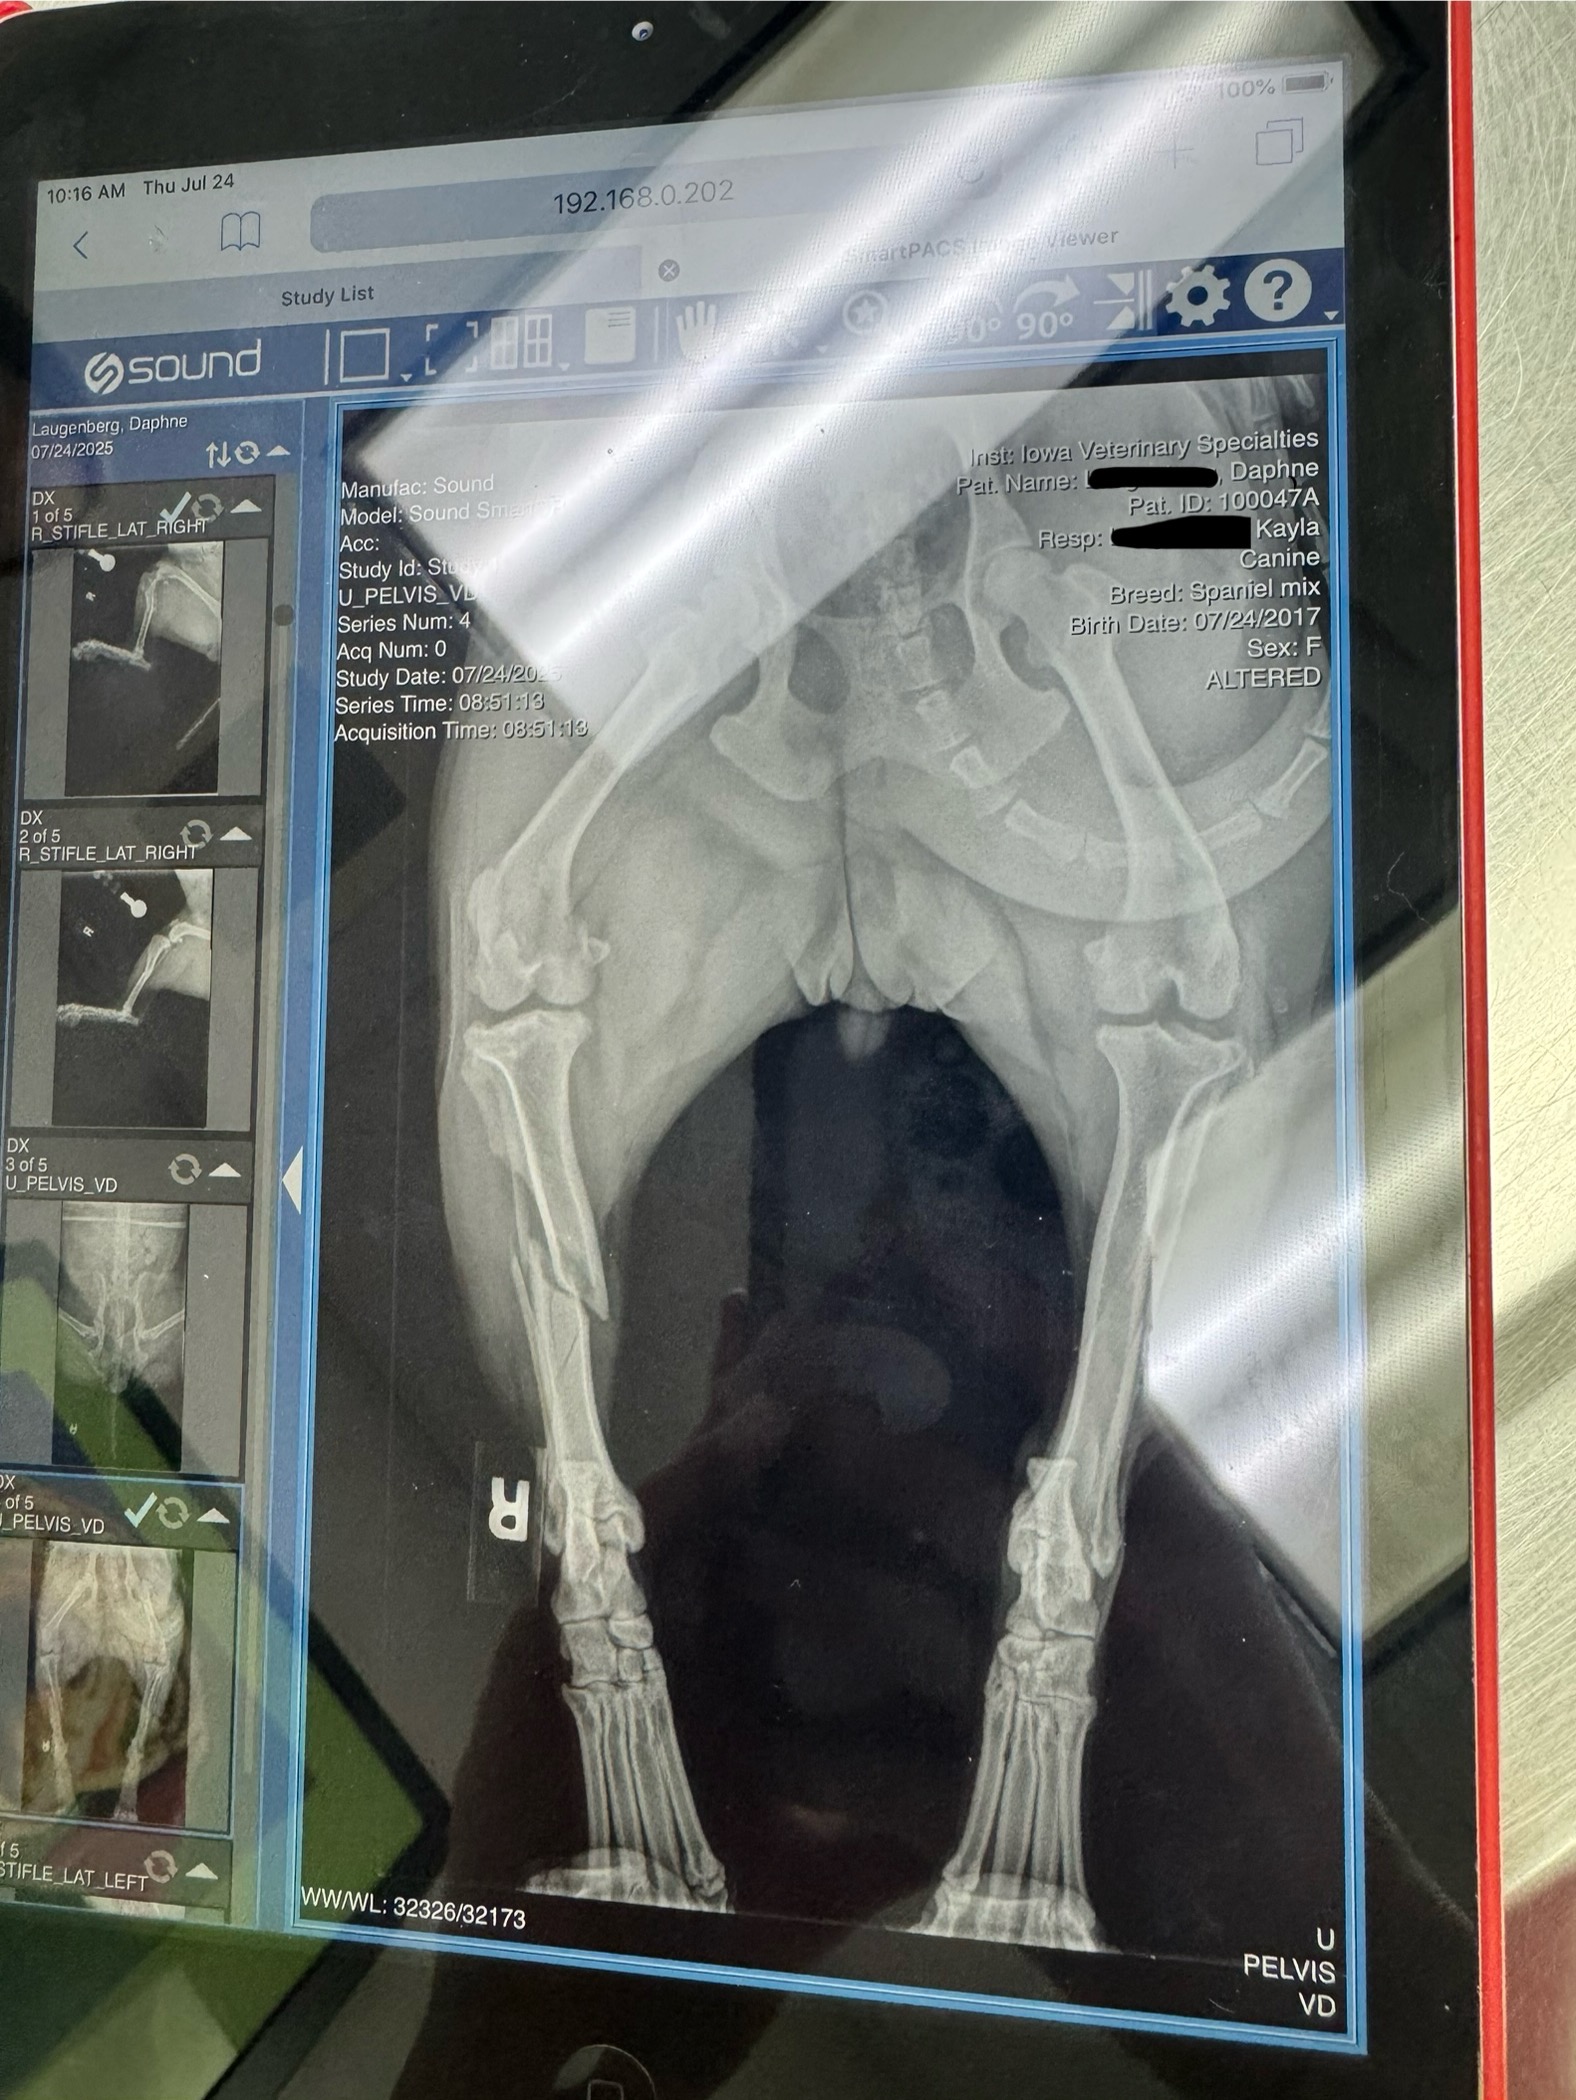

Thursday morning, I woke up to a sound I never want to hear again… Daphne yelling in pain. She either jumped on or off my bed and landed wrong. We went straight to the emergency vet and came to find out she fractured her back right leg in two places. My options were surgery or amputation. She is now getting the best care possible and awaiting surgery.